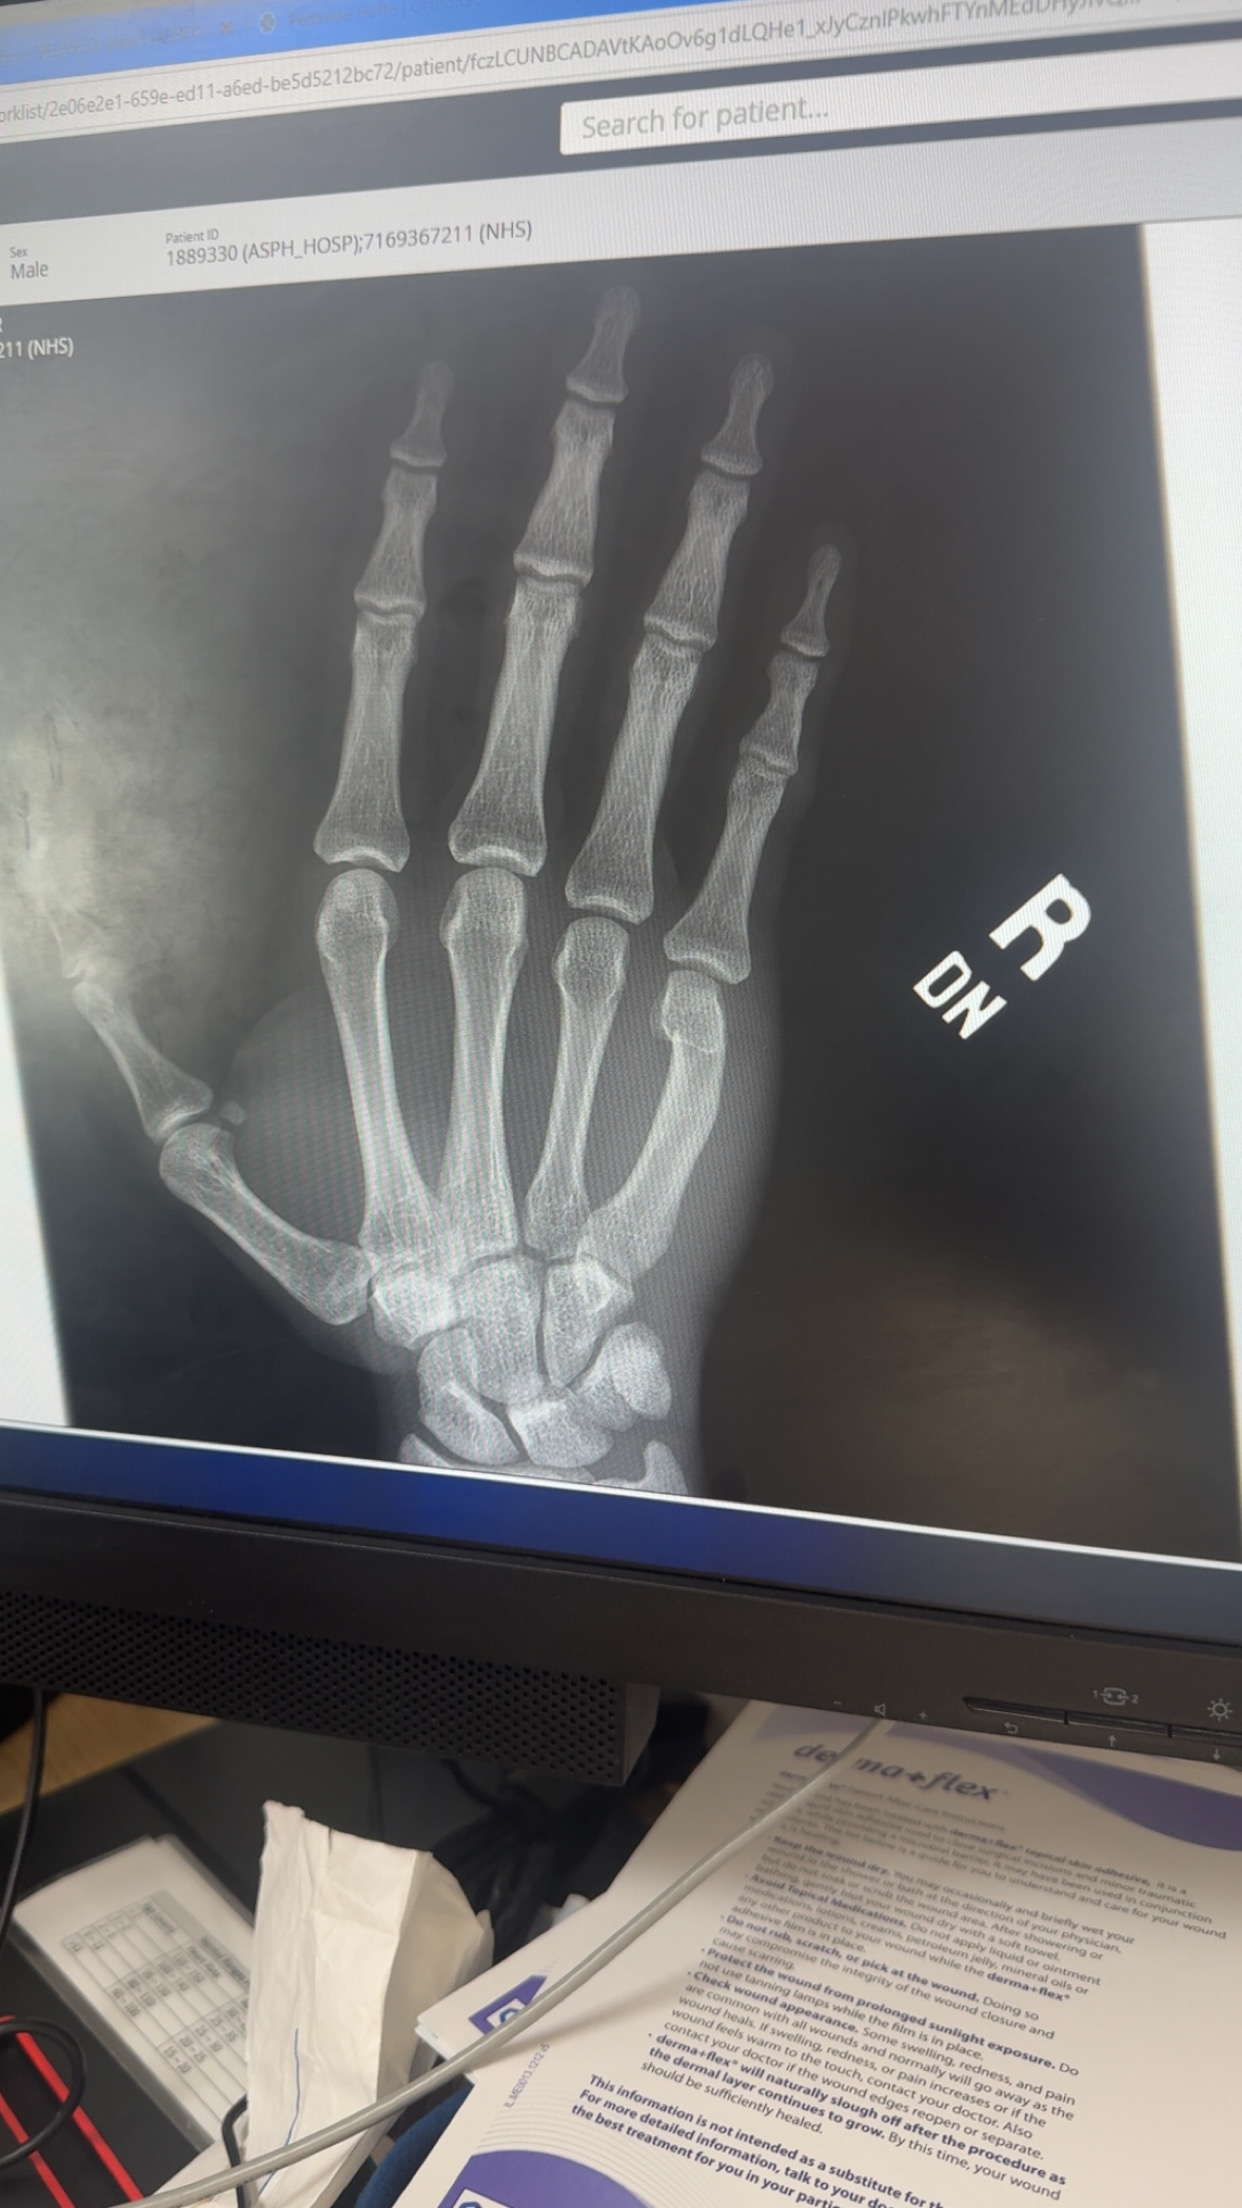

Bone age x ray

IMG 2307

Fractured my knuckle cause was beefing some bus driver and I got this x ray, any high iq niggas can tell me my bone age ? I’ve grown a cm in last month

Second picture u can slightly see wrist, fully closed

yh gemini said fully closed and gpt and claude said not fully closed yet but close. heard hands fuse before elbows and legs so i may b able to squeeze an inch or 2 and get to like 6'1 w tha hgh im taking. If not idrc tm either tho